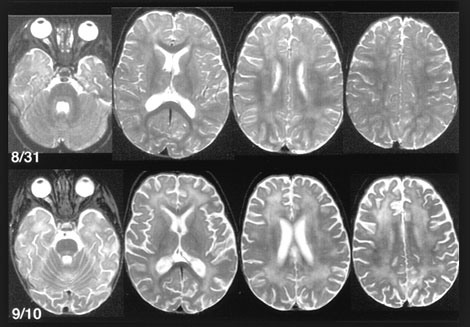

Chẩn đoán hình ảnh trên hệ thần kinh trung ương chỉ là thông tin có giá trị một mức độ nào đó mà thôi. Các hình ảnh MRI thường chỉ ra hình ảnh tổn thương chất trắng lan tỏa không đặc hiệu. Não úng thủy và phù não cũng xuất hiện trên hình ảnh, nếu trước đó không có. Không có dấu hiệu màng não hay tăng sáng trong nhu mô não.

| Hình Tổn thương trên bệnh nhi 11 tuổi nhiễm do tác nhân B. procyonis |